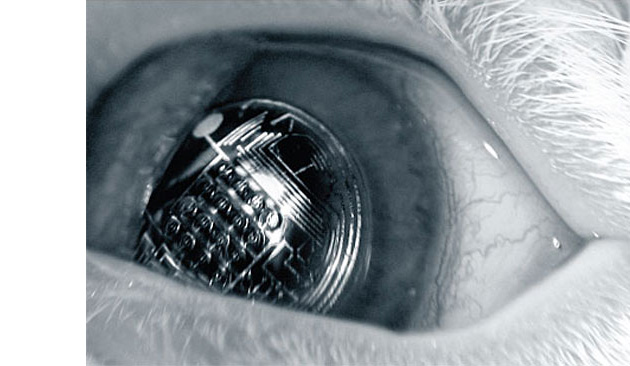

Разработчики утверждают, что их кибер-глаз может поддерживать голосовую связь со своим носителем и содержит единственный источник света. Такую линзу, например, можно использовать в качестве дополнительного дисплея для видеоигр в сочетании со звуковой сигнализацией.

Кроме игрового применения, новая контактная линза со встроенной электроникой может послужить и в медицинских целях. В данный момент разработчики экспериментируют с линзой, используя ее в качестве сенсора для измерения уровня сахара в крови у диабетиков. Теоретически, встроенная в линзу техническая «начинка» способна измерить уровень сахара и передать информацию на внешний компьютер для контроля. После проведения анализа новая линза может предупредить пациента о ненормальном состоянии уровня сахара звуковым сигналом.

На сегодняшний день у создателей удивительной линзы обозначились три проблемы, которые они надеются решить в ближайшее время. Первичной задачей исследователи обозначили проблему несовместимости микросхем с контактными линзами. Далее они намерены решить проблему физических ограничений – поскольку линза и электроника находятся очень близко к роговице глаза, изображение должно фокусироваться непосредственно на сетчатке с помощью дополнительных микролинз или маломощных лазеров. И, наконец, ученые планируют придумать специальные компоненты для линзы, которые должны защищать глаз от химикатов и механических воздействий извне, оставаясь полупрозрачными.